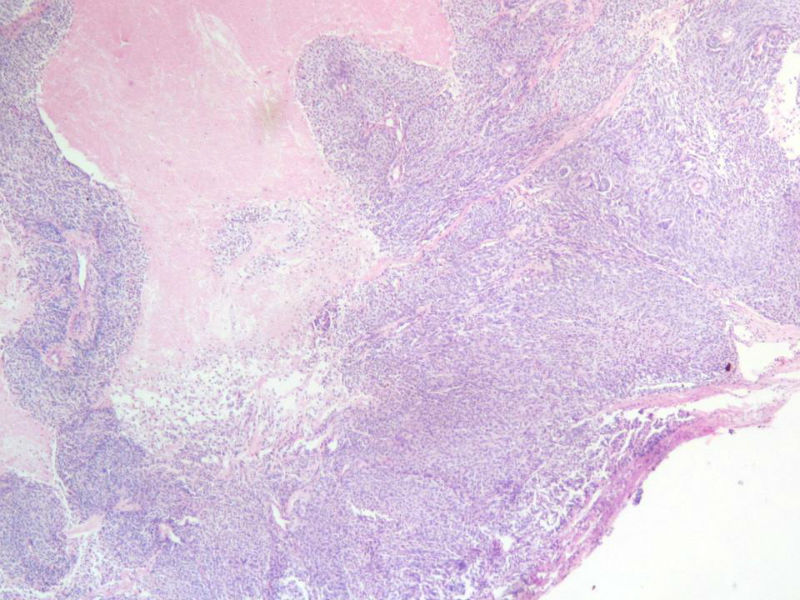

女,64岁,头晕半月,CT检查颅内左颞叶占位,侵犯颅骨和颞肌,手术切除肿物。肉眼,灰白色结节状肿物,3X3X2厘米,边界不清,切面灰黄色,质软。

特别提示:手术前曾做过介入肿瘤栓塞。镜下核分裂15/HP。脑左颞部占位图1

梭形细胞与上皮样漩涡状结构,富于细胞,见个别沙砾体,并见肿瘤性坏死。颅骨及其横纹肌等软组织内见肿瘤呈侵袭性生长。但细胞异型性不是很大。鉴别:

1)恶性脑膜瘤

2)非典型性脑膜瘤

由于非典型性脑膜瘤也可以发生地图状坏死,甚至侵袭性生长。需要计数核分裂数/10HPF,以资鉴别诊断。